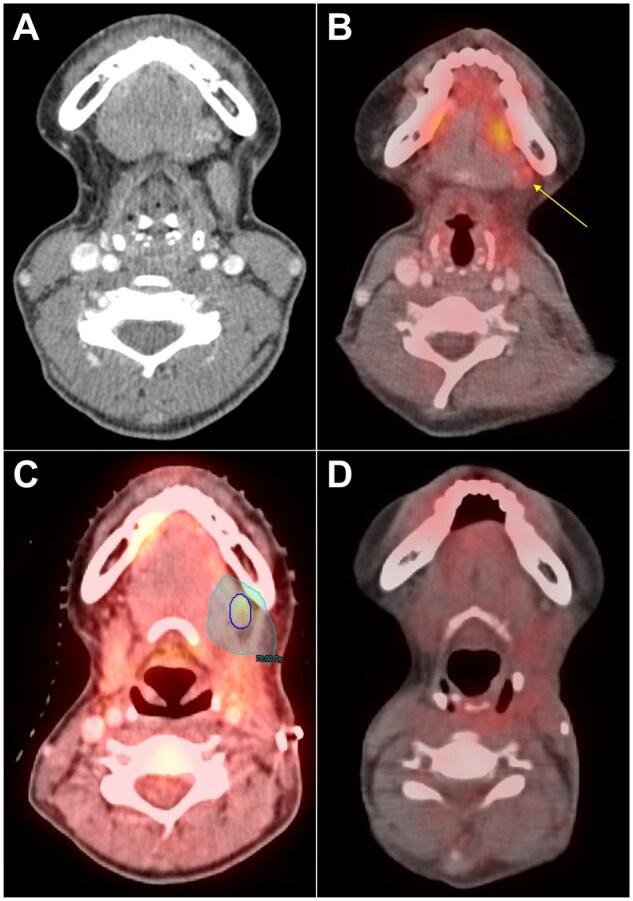

Residual or recurrent cancer after surgery but prior to adjuvant therapy occurs in a proportion of patients with head and neck cancer and may warrant treatment changes. 18-Fluorodeoxyglucose positron emission tomography/computed tomography (FDG-PET/CT) may help to identify residual or recurrent disease but is not routinely obtained. We evaluated the relevance of postoperative FDG-PET/CT in this clinical context.

Of 150 patients, 66 (44.0%) had a management change because of the postoperative FDG-PET/CT findings; 62 (93.8%) had radiotherapy plan changes, 20 (30.3%) underwent additional diagnostic testing, 11 (16.7%) had systemic therapy added or changed, 3 (4.6%) underwent reresection, and 15 (10.0%) switched to palliative-intent treatment. Having a postoperative FDG-PET/CT that resulted in a management change was not significantly associated with cancer recurrence or overall survival (both P > .05).

In patients with resected head and neck cancer, postoperative, pre-adjuvant therapy FDG-PET/CT can alter clinical management and may enable additional personalization of treatment. When practical to obtain without delaying treatment, postoperative FDG-PET/CT may have clinical utility though requires careful interpretation due to the risks of false positives.